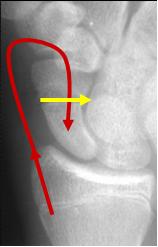

Scaphoid fracture

n Blood supply for the

proximal pole enters at

the waist

n If fracture disrupts

blood supply, proximal

pole at risk for

avascular necrosis